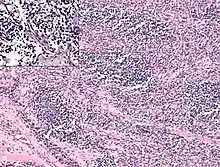

It is generally considered to be a disease of childhood, as the vast majority of cases occur in those below the age of 18. It is commonly described as one of the small-blue-round-cell tumors of childhood due to its appearance on an H&E stain.[4] Despite being relatively rare, it accounts for approximately 40% of all recorded soft tissue sarcomas.[5][6][7]

Rhabdomyosarcoma is often difficult to diagnose due to its similarities to other cancers and varying levels of differentiation. It is loosely classified as one of the small-blue-round-cell tumors due to its appearance on an H&E stain. Other cancers that share this classification include neuroblastoma, Ewing sarcoma, and lymphoma, and a diagnosis of RMS requires confident elimination of these morphologically similar diseases.[15] The defining diagnostic trait for RMS is confirmation of malignant skeletal muscle differentiation with myogenesis (presenting as a plump, pink cytoplasm) under light microscopy.[5] Cross striations may or may not be present. Accurate diagnosis is usually accomplished through immunohistochemical staining for muscle-specific proteins such as myogenin, muscle-specific actin, desmin, D-myosin, and myoD1.[26][35][36] Myogenin, in particular, has been shown to be highly specific to RMS,[37] although the diagnostic significance of each protein marker may vary depending on the type and location of the malignant cells. The alveolar type of RMS tends to have stronger muscle-specific protein staining. Electron microscopy may also aid in diagnosis, with the presence of actin and myosin or Z bands pointing to a positive diagnosis of RMS.[5][35] Classification into types and subtypes is accomplished through further analysis of cellular morphology (alveolar spacings, presence of cambium layer, aneuploidy, etc.) as well as genetic sequencing of tumor cells. Some genetic markers, such as the PAX3-FKHR fusion gene expression in alveolar RMS, can aid in diagnosis. Open biopsy is usually required to obtain sufficient tissue for accurate diagnosis. All findings must be considered in context, as no one trait is a definitive indicator for RMS.